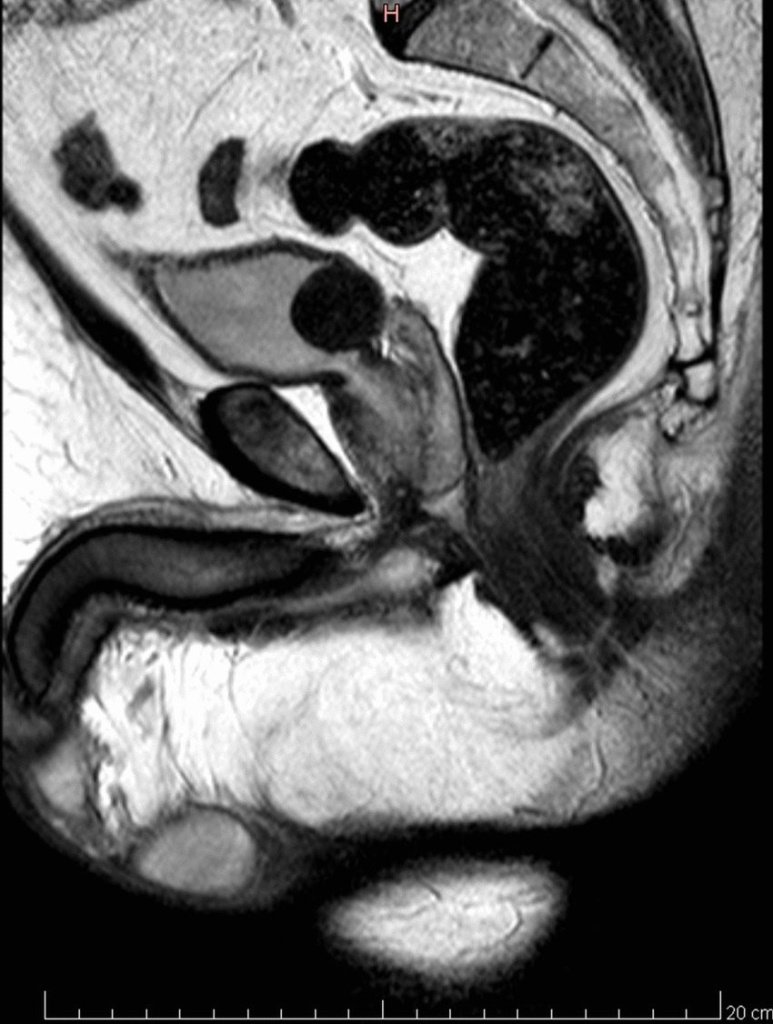

Магнитно-резонансная томография (МРТ) мочевого пузыря — высокоточный метод визуализации, основанный на действии магнитного поля и радиоволн. Во время исследования аппарат создает точные послойные изображения органа без лучевой нагрузки .

При МРТ создаются детальные изображения мочевого пузыря толщиной до 3 мм. Полученные изображения подтверждают нормальное функционирование органа. В случае обнаружения образования МРТ также может показать, насколько далеко заболевание распространилось по стенке или насколько оно потенциально распространилось за его пределы.

МРТ позволяет детально изучить мягкие ткани и дает больше информации, чем УЗИ или КТ при подозрении на опухолевые процессы, утолщения стенки или распространение заболевания на соседние структуры.

Что показывает МРТ

С помощью МРТ мочевого пузыря можно выявить следующие заболевания.